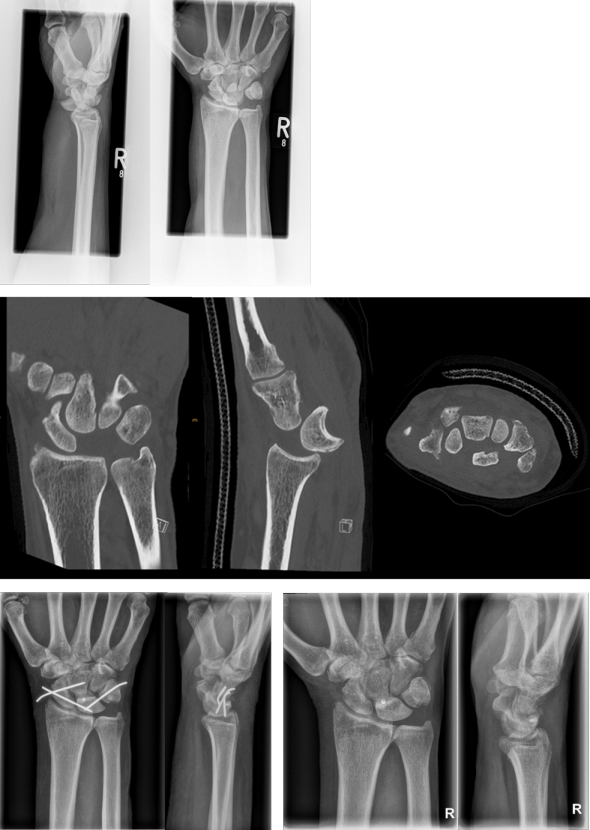

Abbildung 1 [Abb. 1]